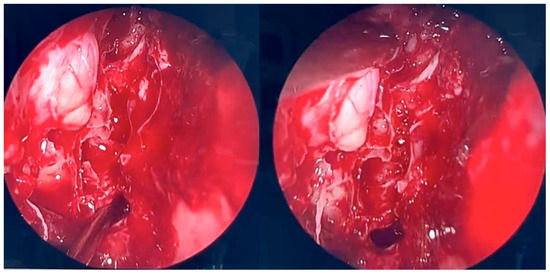

During the second endoscopic procedure, significant postoperative anatomical alterations were observed, including extensive scarring and multiple synechiae. A defect of the medial orbital wall was identified. The underlying bone was visualized and found to be covered only by periosteum. Using a diamond burr, a portion of the bony boundary of the frontal recess was carefully removed to create a surgical access route toward the lesion previously identified on CT and MRI imaging. The lesion was located in the superomedial quadrant of the right orbit, between the medial and superior rectus muscles and adjacent to the retrobulbar segment of the optic nerve. The orbital periosteum was incised, and orbital fat was gently displaced to access the lesion. The pathological tissue was successfully removed and sent for histopathological examination. A nasal dressing was applied to complete the procedure.

Figure 4. Endoscopic surgery: intraoperative view after removal of fungal infiltration to the level of the skull base. Opening of the sphenoidal sinus seen inferiorly (6 o’clock position). The upper-left part of the picture (11 o’clock position) shows the site of orbital periosteum incision with partial herniation of orbital fat into the ethmoid cavity. Two images obtained from the same projection.